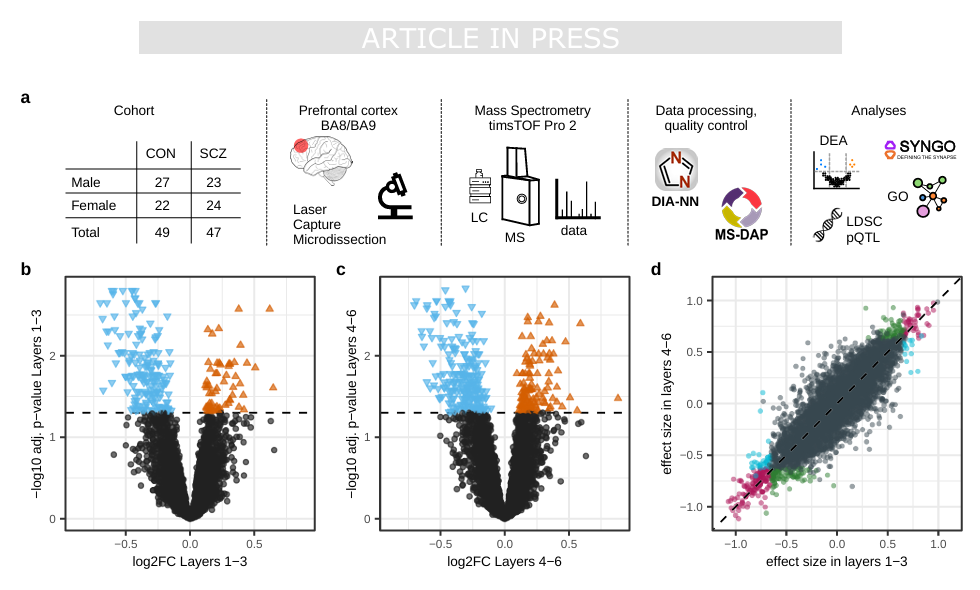

08 (NAT COMMUN) 人类大脑前额叶皮层蛋白质组学揭示精神分裂症中受损的能量代谢和神经元功能

8. (NAT COMMUN,IF:14.7) 人类大脑前额叶皮层蛋白质组学揭示精神分裂症中受损的能量代谢和神经元功能

08 (NAT COMMUN) 人类大脑前额叶皮层蛋白质组学揭示精神分裂症中受损的能量代谢和神经元功能

8. (NAT COMMUN,IF:14.7) 人类大脑前额叶皮层蛋白质组学揭示精神分裂症中受损的能量代谢和神经元功能